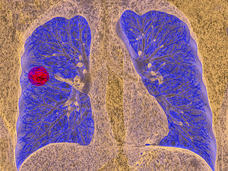

Selpercatinib Shows Promise against Lung Cancers with Alterations in RET Gene

The investigational drug selpercatinib may benefit patients with lung cancer whose tumors have alterations in the RET gene, including fusions with other genes, according to results from a small clinical trial.